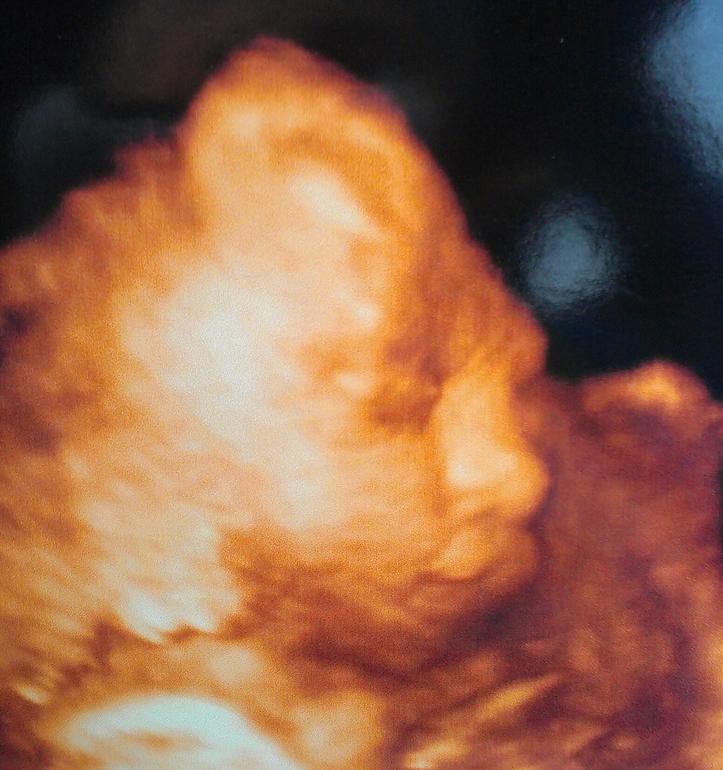

Срок по узи на 2 дня больше, чем по М. Предв.вес 880 гр. Большой мальчик, уже 25,6 нед. :) Пришли на узи, а наш мальчик спит, уткнувшись носом в плаценту, фото личика не сделать. Пришлось тормошить его минут 10, потом подвинулся, пару раз пнул, позевал и снова уснул )))) Но фото сделали к счастью. Похож на папу на этих фото. Фото под катом.